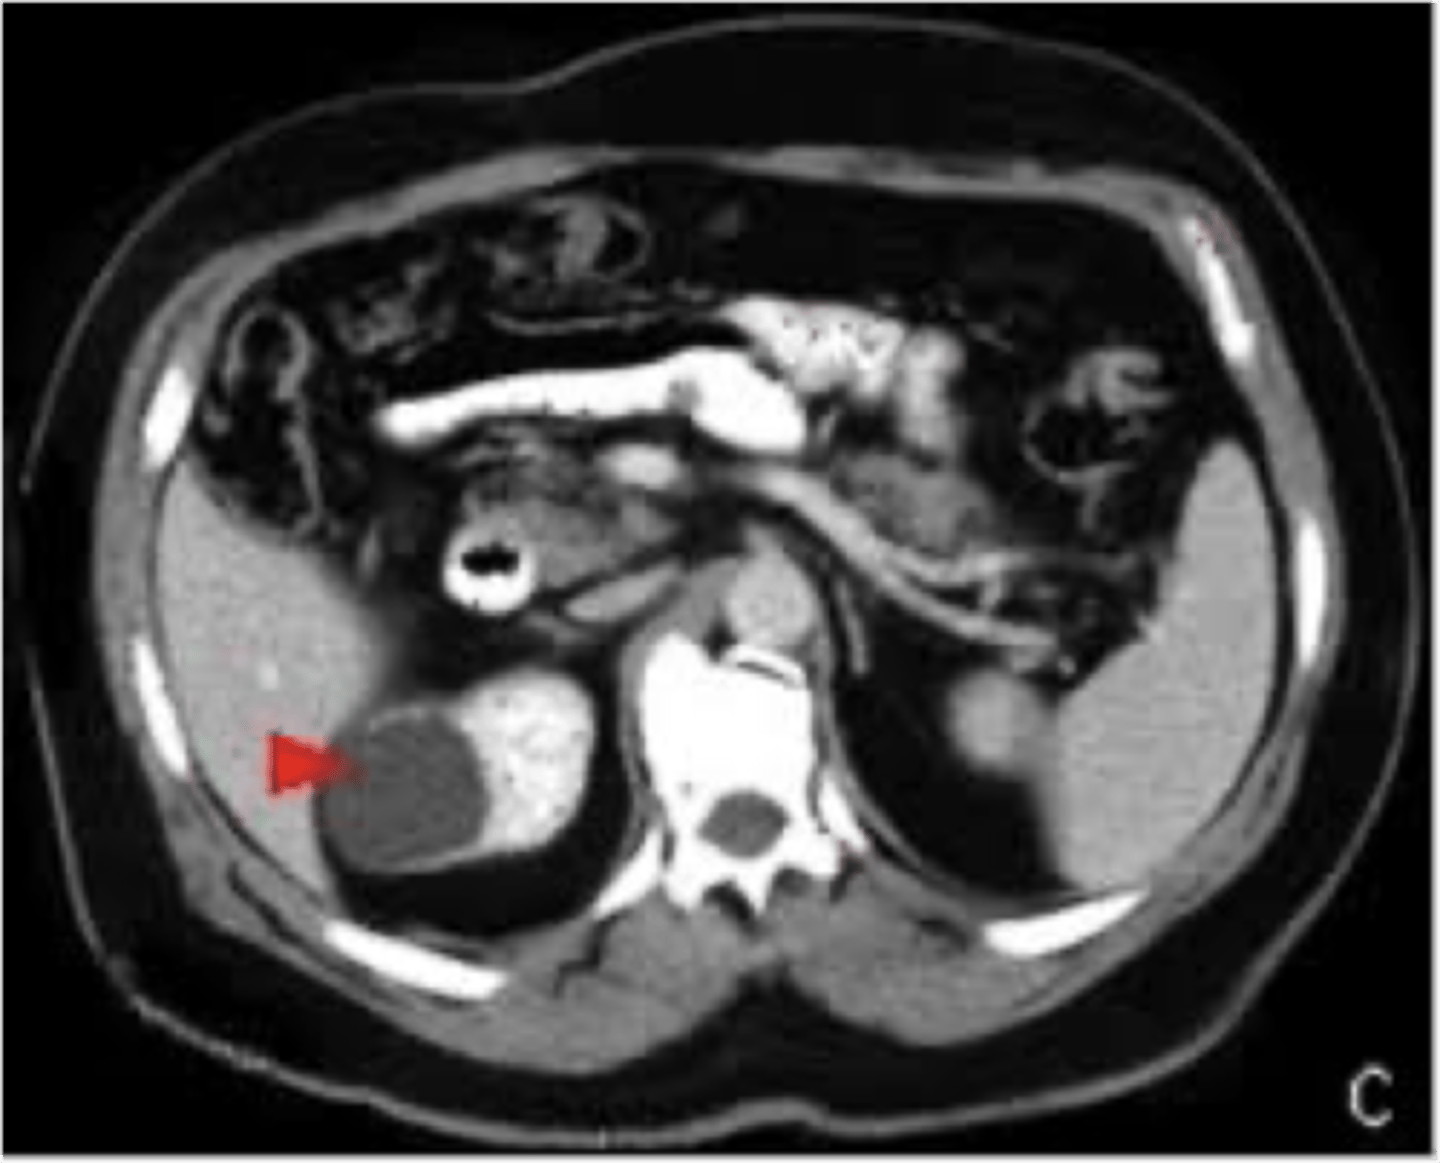

simple renal cyst

ID